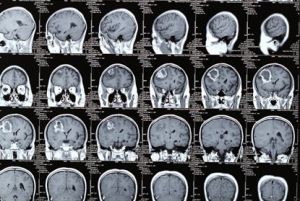

其他輔助檢查:X線顱骨平片上可見額頂骨或其他部位有單發或多發的病灶,表現為邊緣較整齊或穿鑿樣的圓形、橢圓形片狀低密度區或骨缺損,其中有大小及形狀不等、游離的塊狀高密度死骨。CT及MRI檢查也可有病灶區的骨缺損及游離死骨表現,其主要特點是可以發現硬腦膜外、下及顱內的病變部位、範圍,MRI影像上更可清楚分辨出硬腦膜外或下的病變。

顱骨結核進一步發展,病變向硬腦膜外蔓延,當炎症穿透硬腦膜後結核桿菌侵入顱內,引起顱內併發症,最常見的是結核性腦膜炎和顱內結核瘤,二者均可使病情加重,危及病人的生命。當並髮結核性腦膜炎時,病人突然發生劇烈頭痛、噴射性嘔吐、高熱、體溫可達39℃以上,抽搐、昏迷。查體可發現項強,克匿格(Kernig)征陽性。外周血象檢查白細胞增多可達15×109/L~20×109/L(1.5萬~2萬/mm3),以淋巴細胞增多為明顯。血沉加快,可在2030mm/h以上。腰椎穿刺檢查時腦脊液壓力明顯增高,可達2.45kPa(250mmH2O)以上,腦脊液化驗檢查可見略混濁呈毛玻璃狀,靜置數小時後可有薄膜形成,白細胞增多但常在0.5×109/L(500/mm3)以下,以淋巴細胞為主,糖及氯化物含量降低,蛋白含量明顯增高。腦脊液塗片染色鏡檢有時可查到結核桿菌,動物接種可有陽性發現。此時應採取降溫,抗癲癇藥物,靜脈輸入20%甘露醇250ml3~4次/d,降顱壓及地塞米松20mg/d;每3~5天行鞘內注射頭孢曲松40mg及地塞米松5mg等治療措施。並發顱內結核瘤時表現為進行性顱內壓增高及顱內占位病變的症狀與體徵。CT及MRI檢查可顯示圓形或橢圓形均勻一致高密度或混雜密度區,腦室受壓變形,中線結構向對側移位,可明確病變部位及範圍,在局部病灶清除前或術後傷口尚未癒合時,可先行抗結核藥物及降顱壓藥物治療,待傷口癒合後顱內占位仍不好轉再行開顱切除。如原傷口尚未癒合而顱內病變惡化,可先鑽顱穿抽膿,如必須開顱手術時,應儘量避開原傷口開顱,或暫時作顳肌下減壓術以緩解病情。顱骨結核如早期作徹底病灶清除咬除顱骨時,術後僅遺有顱骨缺損。但如並發腦膜炎則甚易造成顱底腦池及腦表面蛛網膜粘連,即使炎症被控制,也常遺留癲癇及交通性或梗阻性腦積水。結核球切除術後也可遺一些神經系統功能障。